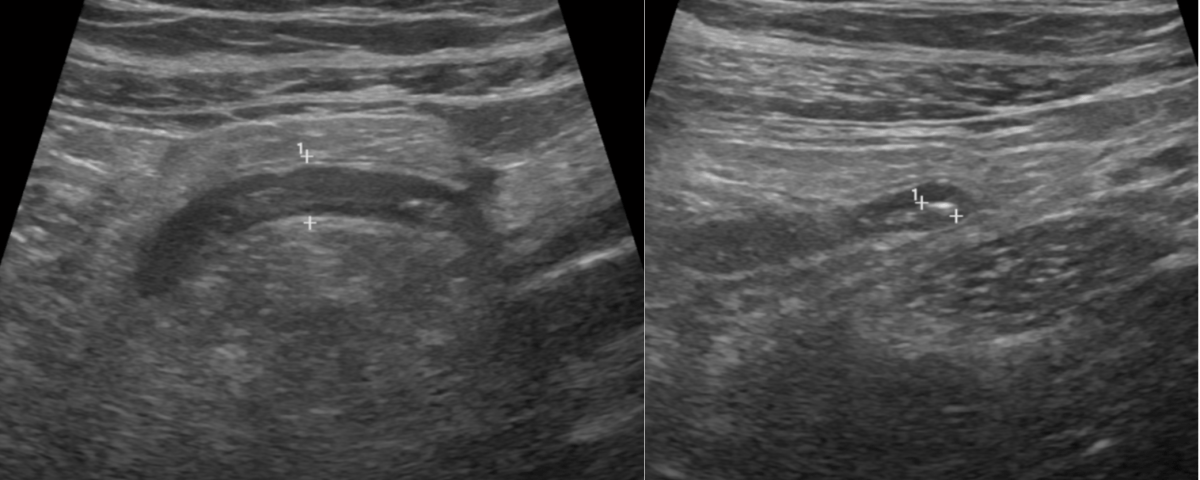

Atypical CEUS Pattern as a Diagnostic Clue in a Focal Liver Lesion [February 2026]

March 30, 2026